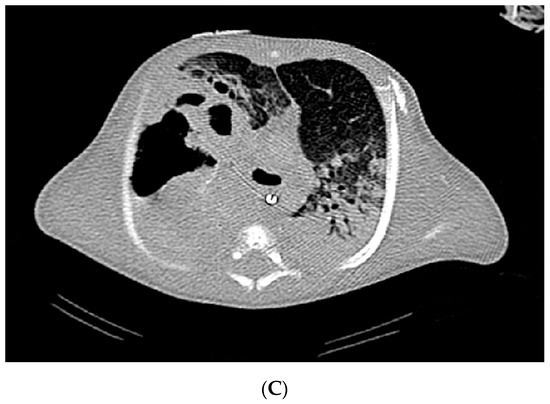

2. Case Report